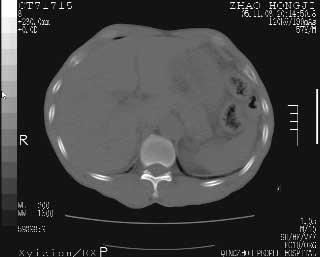

临床资料:男性,57岁,上腹部疼痛并5天,突然加重并延及全腹伴恶心5小时入院。胰淀粉酶化验在正常范围。检查:腹肌紧张,全腹压痛、反跳痛,尤以右上腹部为著。肠鸣音减低。血常规:wbc14.6x10/9, n:11.3x10/9 ,血压:135/90mmhg. 胸部透视:腹部肠腔轻度张气,未见其它异常改变。

胰腺形态规则,胰周脂肪间隙清晰,结合临床可排除急性胰腺炎

从图提示我同意空腔脏器穿孔的诊断,来源肠道{由于病程较短,故没能见到肠系膜聚局的征象}。

肝缘见少许气体,胰尾部见少许气体包饶(蓝色圈),12指肠上部或球部邻近胆囊周边也可见少许气体影(黄色圈),并忖托出胆囊壁,12指肠远段肠道内未见明显气体(白色箭)。

肝脏前缘见少量积气、胰尾部见少许气体包饶,肾前筋膜未见增厚,临床淀粉酶不高,意见:上消化道穿孔。

消化道穿孔。12指肠球部周和胰周积气考虑12指肠穿孔可能性大。

入院3小时后行剖腹探查术,见腹腔内大量脓性混浊液约1000ml,十二指肠球部溃疡穿孔,溃疡面约2.5x2cm,穿孔直径约0.6cm。胃内容物外益,周围组织炎性水肿明显。行十二指肠穿孔修补术。术后诊断:

1、十二指肠溃疡穿孔

2、弥漫性腹膜炎

对于少量的腹腔游离气体,ct检查较普通透视有绝对的优势,它不仅可以看到肝脏前上缘的气体,而且还能够看到小网膜区的游离气体。从而可以肯定诊断。各位分析战友的很好,感谢大家的参入!